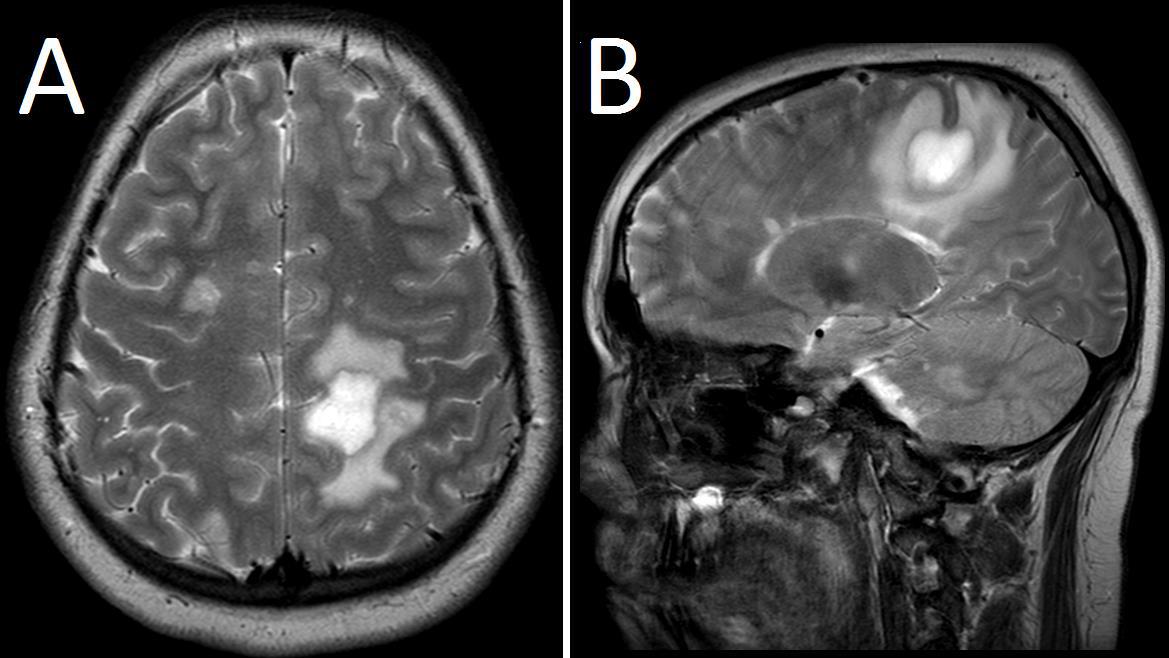

Poniższy obraz badania MR głowy wykonano u 12-letniego chorego (A przekrój poprzeczny, B przekrój strzałkowy). Wskaż najbardziej prawdopodobne jest rozpoznanie: